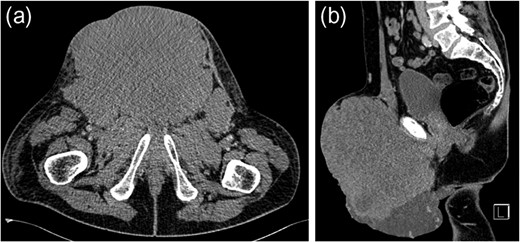

Seminomatous germ cell tumours characteristically affect men in their second-to-fourth decades, presenting as a testicular mass. Metastases when present are usually seen in para-aortic lymph nodes. These tumours are difficult to diagnose clinically and histologically when the presentation is unusual. We describe a seminoma presenting in a 61-year-old male as an inguinal mass with associated lymphadenopathy resembling lymphoma. Past medical history included ipsilateral cryptorchidism and orchidopexy. The tumour responded well to conventional chemotherapy.

Testicular tumours account for approximately 1% of all malignancies in men [1]. Up to 95% of testicular tumours are germ cell tumours (GCTs), which are subdivided into seminomatous and non-seminomatous tumours [2]. Histologically, seminomas may be further divided into three subtypes: classic, anaplastic and spermatocytic. Pure seminomas do not produce a specific tumour marker subset, but by definition have low levels of alpha-fetoprotein (AFP) and can have normal or mildly elevated beta-HCG (beta-subunit of human chorionic gonadotropin) [3]. Risk factors for the development of GCTs include cryptorchidism, Klinefelter's syndrome and testicular dysgenesis [4]. Testicular tumours commonly metastasize along gonadal vessels to the retroperitoneal lymph nodes [5]. Inguinal metastasis from a testicular seminoma is rare and likely related to previous inguinal or scrotal surgery causing disruption in normal lymphatic drainage [6]. We report a case of a massive seminoma presenting with primary inguinal lymph node metastasis in the absence of retroperitoneal lymphatic spread.

Testicular tumours account for approximately 1% of all malignancies in men, and they are the most common solid malignancy that affect males between 15 and 35 years old [2]. Up to 95% of testicular cancers are GCTs and the most common site for metastatic spread is the retroperitoneal lymph nodes. Inguinal lymph node metastasis is a rare occurrence and may be secondary to retrograde extension from significant retroperitoneal metastatic burden [5]. Primary involvement of inguinal nodes may be due to direct tumour invasion into the epididymis, breaching the scrotal wall or extension towards the vas deferens [7]. The large size of the tumour in our case suggests it is highly likely inguinal node involvement was via this route.

However, inguinal metastases have been reported in up to 10% of patients with a testicular tumour who have previously undergone orchidopexy or scrotal surgery [8]. It has been suggested that previous inguinal or scrotal surgery may lead to alteration in the usual patterns of lymphatic drainage. In our case, the history of orchidopexy for cryptorchidism could have been a significant factor for the absence of retroperitoneal lymphadenopathy despite the significant tumour burden at presentation. The overall risk of developing testicular cancer is greater in patients with previous cryptorchidism, occurring in 10% of GCTs [9]. Our case suggests that patients who have previously undergone inguinal or scrotal surgery may have alterations in normal lymphatic drainage leading to rare and atypical presentation of metastatic disease despite high tumour burden.